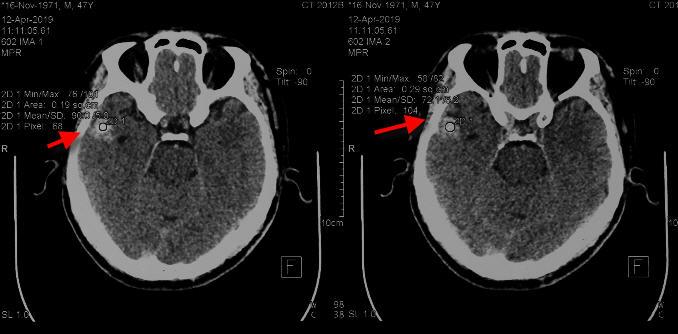

2019年2月25日头颅平扫+图像重组CT片示:左额部头皮软组织肿胀,右侧颞叶见类圆形高密度影,中线结构居中。

2019年2月26日头颅平扫+图像重组CT片示:左额部头皮软组织肿胀较前恢复,右侧颞叶见类圆形高密度影,较前无动态变化。

2019年4月12日本院头颅平扫+图像重组CT片示:右侧颞叶见类圆形高密度影,较前无动态变化。

受伤当天头颅CT片显示右侧颞叶见类圆形高密度影

受伤当日头颅CT片显示右侧颞叶见类圆形高密度影 4月12日头颅CT片未呈现动态变化